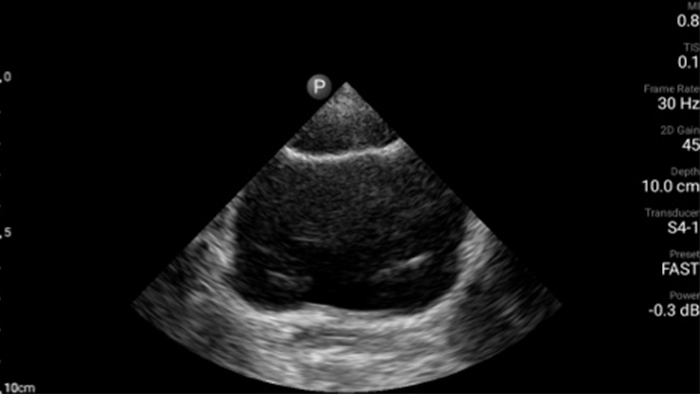

Lumify handheld ultrasound offers images that enhance diagnostic confidence.

See more when it counts

Lumify can help you make real-time decisions with more confidence, from assessment to recovery. Reveal the subtle details of an image, uncover enriched tissue definition with multiple angles and much more.

Emergency medicine